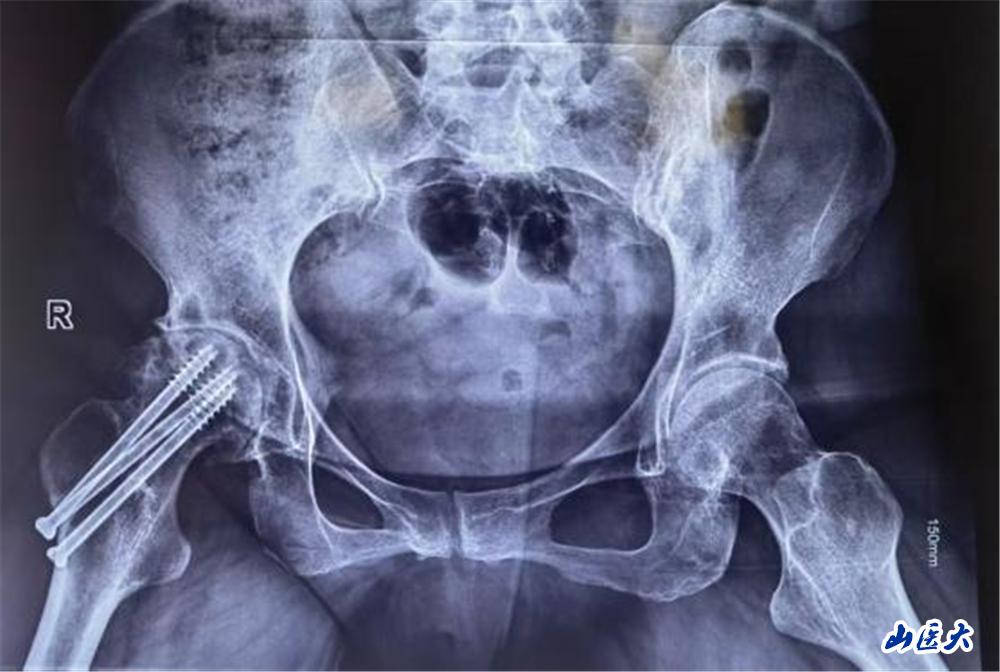

陈大姐饱受股骨头坏死折磨3年,近一个月疼痛加重,行走困难。面对患者强烈的保髋愿望,医疗团队术前通过影像学检查及血管评估,精准分析患者股骨头坏死范围及血供情况,为其量身定制了“带血管蒂的腓骨瓣移植”手术方案。这一术式能重建股骨头血运,延缓甚至避免关节置换,但对医生的显微外科技术要求极高。

手术当日面临巨大挑战,医疗团队需在患者腓骨处截取长约6cm的带血管骨瓣,并在显微镜下将细如发丝的旋髂外侧动脉与股骨头供血血管吻合。5个半小时的奋战,每一步都考验着团队的默契与技艺。